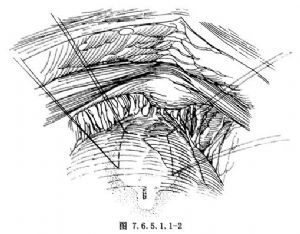

2.切口 下腹正中切口,顯露膀胱,並遊離膀胱尿道連接部(摸清膀胱內氣囊可幫助定位)。在半充盈的膀胱前壁預定做膀胱瓣的四角縫4針4號絲線作留置線,瓣的長度約5cm左右,寬度以能包繞導尿管爲準,遠側邊恰在尿道內口水平(圖7.6.5.1.1-2)。